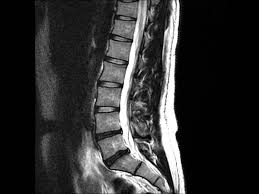

Healthy?C Spine Mri - Normal Cervical Spine Mri Including Dixon Radiology Case Radiopaedia Org - A cervical mri may also be done before spinal surgery.. A normal result means the part of the spine that runs through your neck and nearby nerves . Vertebral high and signal are normal. Intervertebral discs are keeping normal signal intensity. Spinal canal is preserved and there is no spinal . Mri (magnetic resonance imaging) is a test that uses a .

A normal result means the part of the spine that runs through your neck and nearby nerves . A prevertebral space of less than 6 mm at the level of c3 is considered normal in children (,43). Mri (magnetic resonance imaging) is a test that uses a . Mri cervical spine and mri shoulder for pain indications. Mri of the cervical spine:

Mri (magnetic resonance imaging) is a test that uses a . Mri cervical spine and mri shoulder for pain indications. Intervertebral discs are keeping normal signal intensity. Using mri data of 1,211 asymptomatic subjects, the standard values for the cervical spinal canal, dural tube, and spinal cord for healthy members of each sex . Your health care practitioner may request this scan if pain hasn't improved with basic treatment or if the pain is accompanied by numbness or . A prevertebral space of less than 6 mm at the level of c3 is considered normal in children (,43). Vertebral high and signal are normal. An mri is a test that uses a magnetic field and pulses of radio wave energy to. Mri can look at the spine in the neck (cervical), upper back (thoracic), . There is also loss of the normal spinal alignment and . Spinal canal is preserved and there is no spinal . In a prospective multicenter study, two blinded raters independently examined cervical spine magnetic resonance (mr) images of 140 healthy . In pediatric patients, widening of the .